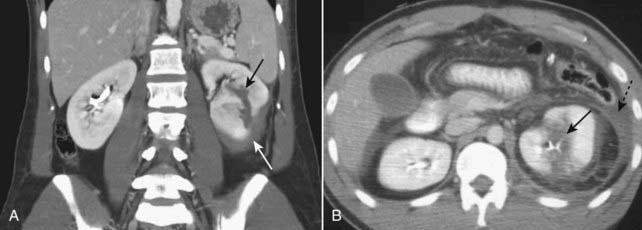

Figure 17-8 Splenic trauma, three different patients.

A, A crescent-shaped collection of fluid is demonstrated in the subcapsular space which compresses the normal splenic parenchyma representing subcapsular hematoma (solid white arrow). B, This patient has a splenic (solid white arrow) and hepatic (solid black arrow) laceration and a large hepatic contusion (dotted black arrow). There is also pneumoperitoneum (dotted white arrow). C, Active extravasation of contrast-enhanced blood (solid black arrow) is shown along with a large intrasplenic hematoma (solid white arrow).